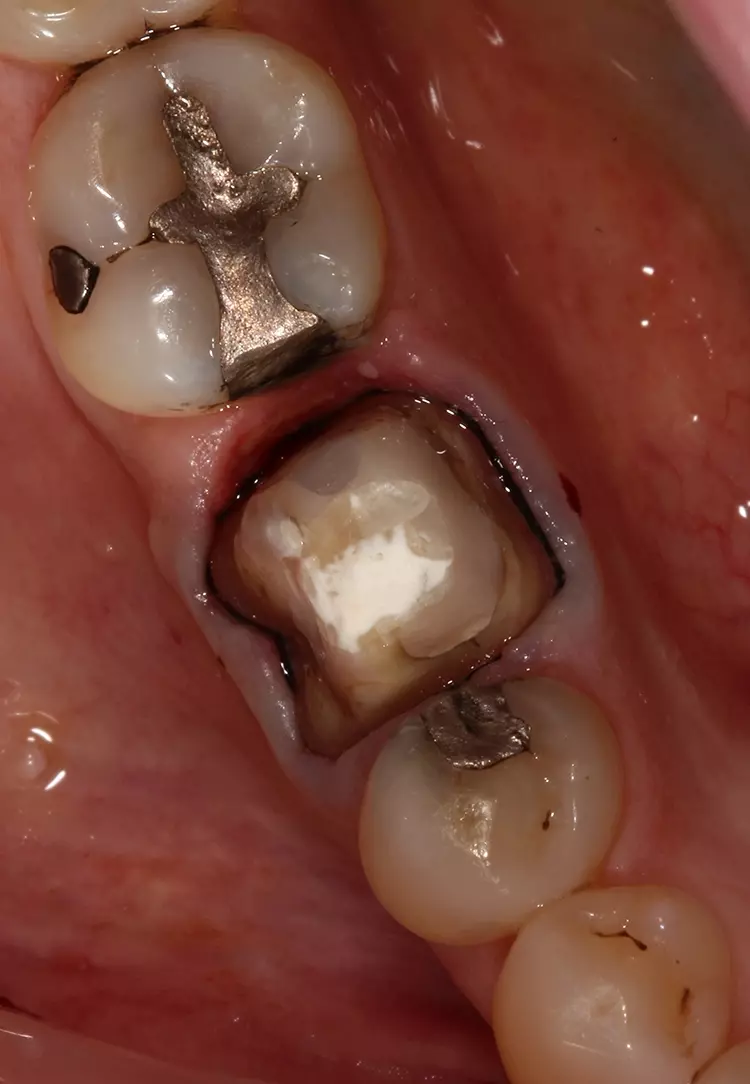

Die Präparation für die neue Krone erfolgte mit konischen Fräsern grober und mittlerer Körnung (850.014C/M, Solo Diamond). Nach der Kariesentfernung war eine Anhebung der tief liegenden Kavitätenränder erforderlich, die ebenso wie auch der Aufbau des restlichen Stumpfes mit VisCalor bulk (VOCO) erfolgte. Um eine Weichgewebskonditionierung zu ermöglichen, wurde eine provisorische Krone hergestellt, die der Patient vor der digitalen Abformung einige Wochen getragen hat (Abb. 2a und 2b).

In der nächsten Sitzung wurde nach der Entfernung des Provisoriums eine gezielte Reinigung durchgeführt, gefolgt von der digitalen Abformung (Abb. 3). Zur Darstellung der Präparationsränder wurde vorbereitend ein Retraktionsfaden der Größe 000 mit einem Retraktionsfadenstopfer um den präparierten Zahn 46 gelegt (Abb. 4). Anschließend wurde zusätzlich VOCO Retraction Paste mit langsamen kreisenden Bewegungen in den Sulkus eingebracht und in situ belassen (Abb. 5 und 6).

Die klinische Situation mit einem erkennbar erweiterten, trockenen gingivalen Sulkus war ideal für den nachfolgenden intraoralen 3D-Scan (Abb. 7 und 8). Die CAD-Screenshots der mit dem Trios-Intraoralscanner (3Shape) erstellten 3D-Scans bestätigten den klinischen Eindruck (Abb. 9a und 9b).

Im vorliegenden Fall ging es um die Behandlung einer Karies an einem Kronenrand. Nach Entfernung der Krone und der Karies wurde zum Wiederaufbau des Zahnstumpfes das thermoviskose Komposit VisCalor bulk (VOCO) verwendet. Um eine ausreichende Materialstärke des Abformsilikons an den Rändern zu gewährleisten und um dadurch ein Einreißen oder Verziehen beim Entfernen zu verhindern, ist eine Sulkusbreite von 0,2 mm zwingend erforderlich [7].

Die provisorische Krone wurde mit Komposit auf der distalen Seite verstärkt. Zur morphologischen Adaptation des Weichgewebes trug der Patient die provisorische Krone für einige Wochen. So konnten gleichzeitig die Bedingungen für eine präzise Abformung geschaffen werden.

Die provisorische Krone wirkt etwas unförmig (Abb. 2), was auf die mangelnde Ästhetik der ursprünglichen Krone zurückzuführen ist. VOCO Retraction Paste ist ein pastöses Produkt, das in einem Cap zur direkten Anwendung erhältlich ist. Es hat ausgezeichnete adstringierende Eigenschaften und hinterlässt, wie in diesem Fall zu sehen ist, einen trockenen und gut geweiteten trockenen Sulkus – ideale Voraussetzungen für eine hochpräzise Abformung.